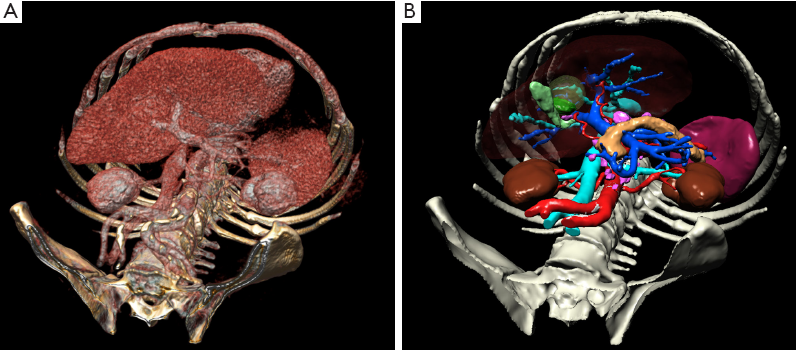

Surface rendering is the first 3D rendering method used for displaying 3D medical images [67, 71]. The surfaces are displayed using segmentation techniques such as thresholding which helps to select only the designated pixels. A virtual light provides surface shading. This method allows presenting only a single surface, which results in the relative advantage of no overlapping tissues. This becomes a limitation, though, when trying to understand the relationships between multiple organ systems. Also, many organs have similar density with the surroundings and as such, they can be difficult to separate. Lastly, true depth perception can not be achieved on 2D displays.

Volume rendering [73, 74] helps visualize complex 3d images. Using a transfer function, different body structures with different pixel intensity values can be displayed with different color and intensity, for example, blood vessel voxels can receive one color and voxels corresponding to bone density can receive a different color. In the case of overlapping structures, this display method is limited when used on 2D displays [75, 76].

A visual comparison between the volume rendering and surface rendering techniques is presented in Figure 2.5.